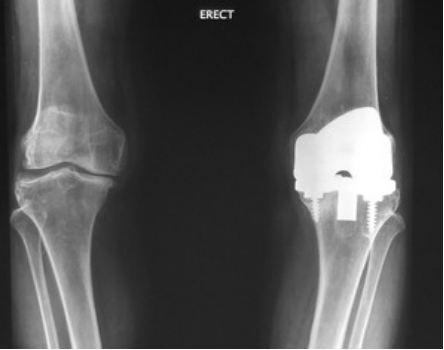

Options to TKR include unicondylar or bicompartment knee replacement. It is possible now to replace a specific compartment of the knee, rather than the entire knee. This procedure can be viewed as a “pre-TKR surgery”. With cruciate preservation and less surgery, recovery is faster. However, patients qualifying for these implants are not common, as they need to be treated earlier rather than wait for all compartments to be involved.